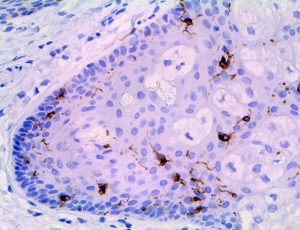

It is the ICU physician who is most likely to witness one of the deadliest manifestations of the abnormal immunological response, the cytokine storm syndrome (CSS). This response is also referred to by some as the cytokine release syndrome (CRS). CSS is characterized by continuous activation and expansion of macrophage and lymphocyte populations, which secrete large amounts of cytokines, causing the cytokine storm. This massive cytokine release is akin to hemophagocytic lymphohistiocytosis (HLH) disease, a syndrome characterized by initial unchecked and persistent activation of cytotoxic T lymphocytes and NK cells.

Clinical and laboratory manifestations of HLH include fever, enlarged liver and/or spleen, neurologic dysfunction, coagulopathy, liver dysfunction, cytopenias (i.e., low levels of erythrocytes, leukocytes, and/or platelets), hypertriglyceridemia, hyperferritinemia, hemophagocytosis, and eventually diminished NK cell activity as the immune system becomes progressively paralyzed. HLH can be familial (primary HLH) or secondary to another disease process (sHLH), such as rheumatic disease, in which it is referred to as macrophage activation syndrome (MAS, characterized by elevated ferritin).